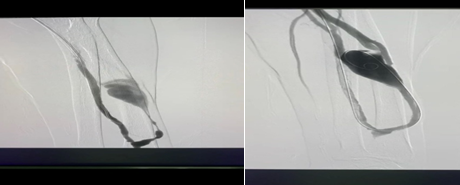

刘老师的动静脉内瘘已使用了7年,去年开始出现了头静脉局部狭窄,需要定期行造影检查及球囊扩张。近期在透析过程中再次出现血流量下降,超声探查提示头静脉狭窄,急需进一步处理,疫情期间,刘老师和家人都表达了希望在我院治疗。我们联系了血管外科贾伟副主任医师,贾大夫很爽快的说“没问题,立马可以过来处理”。经过了CT及新冠核酸检测后刘老师住进了肾内科病房,中午利用午休时间,血管外科贾大夫和程志远医师赶来,顺利的完成了造影剂球囊扩张,刘老师又可以正常的透析了。

术前术后

关奶奶是人工血管内瘘,已使用了4年,每1-3个月需要行一次球囊扩张,因为疫情近期没有复查。在上机时护士发现关奶奶内瘘的震颤及杂音都消失了。超声提示人工血管内血栓形成。关奶奶默默的流了眼泪,说“疫情期间,心情都不好”。有了之前和血管外科合作的经验,我告诉奶奶,我们医院也可以处理,不用到处跑了,奶奶特别高兴,开心的笑了。